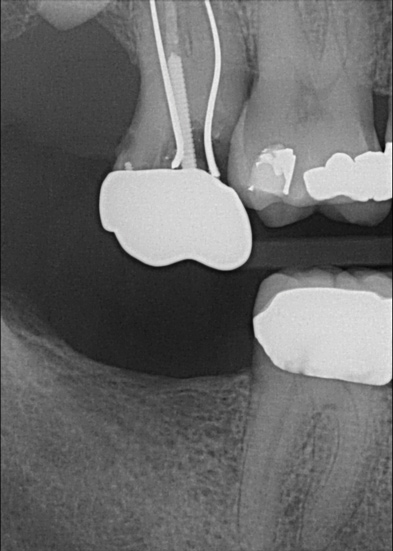

Fig 6. Patient No. 3 presented for an implant restoration at site No. 31 to eliminate pain due to chewing on the ridge from extruded tooth No. 2. Tooth No. 2 was equilibrated to eliminate the patient’s symptoms. In some patients, super-eruption can be severe enough to preclude an implant restoration due to a lack of restorative space.

Figure 6